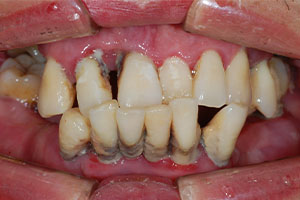

치료증례 전후사진

Before & After